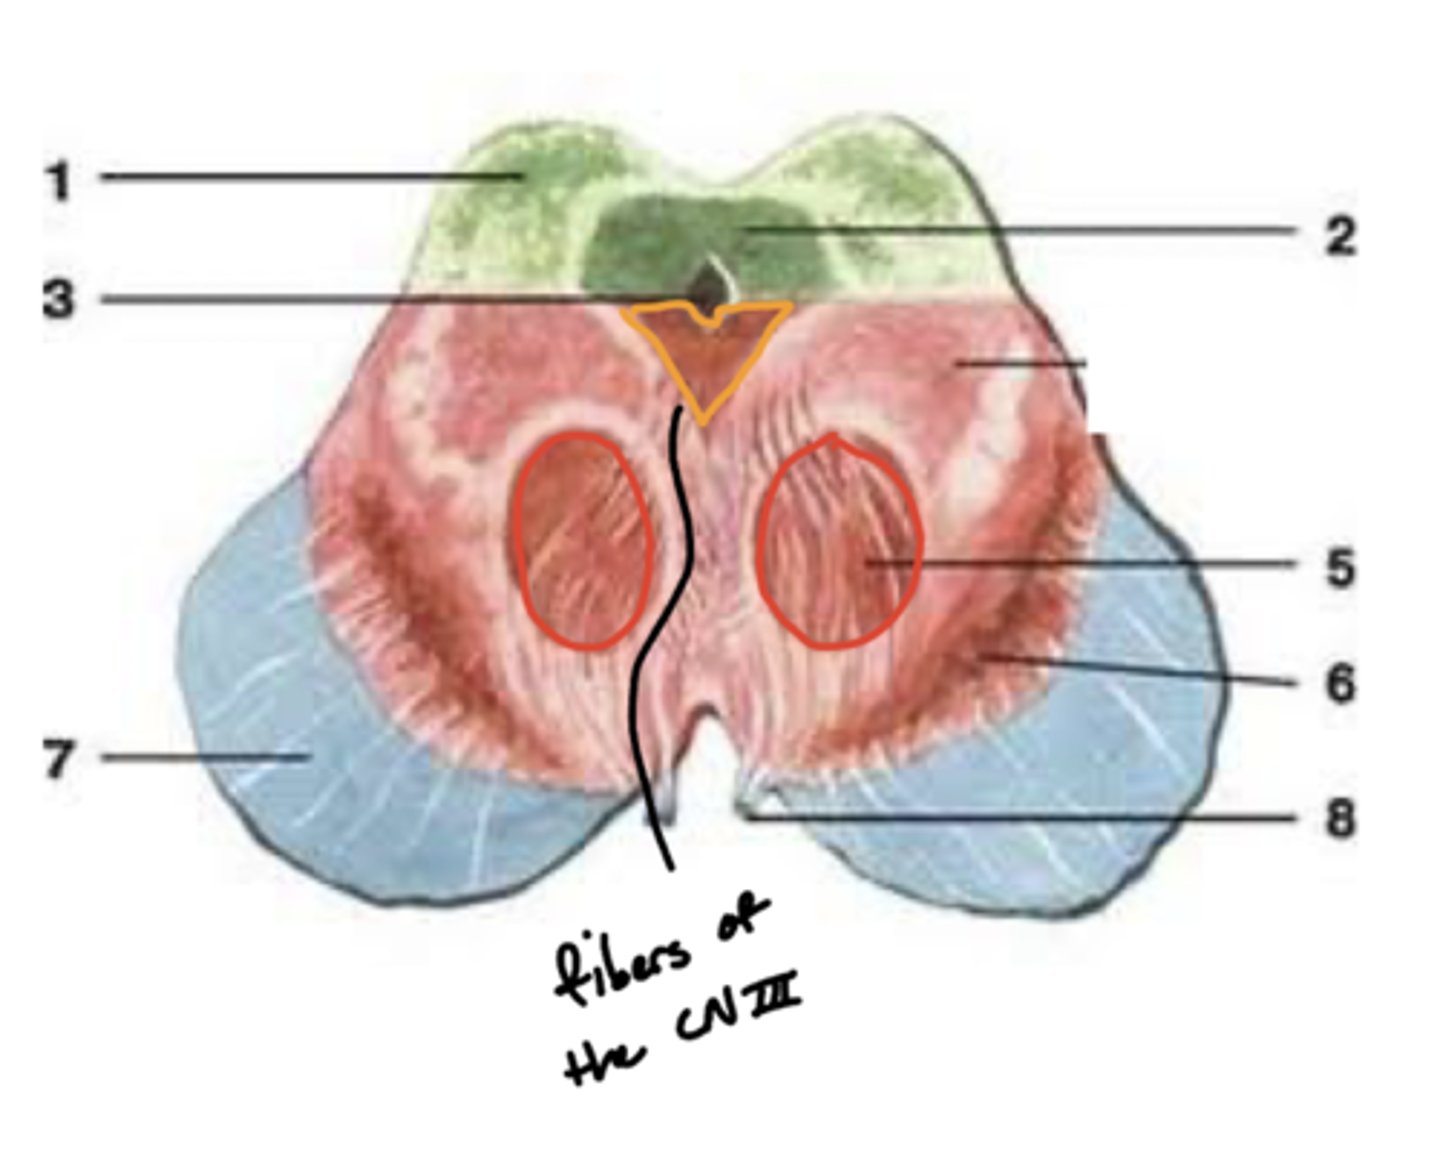

What are the red nuclei?

projection fibers from the (contralateral) cerebral hemisphere down the spinal cord to limbs

image -- 5

What other notable structure should you see if you see two red nuclei?

"if you see two red nuclei you're at the superior colliculus level"

Where does CN III exit the brainstem?

interpeduncular fossa (ventral surface)

Where are the CN III and IV nuclei?

tegmentum mesencephalon

CN III -- anterosuperior

CN IV -- posteroinferior

What is the floor of the 4th ventricle?

tegmentum pons

image -- green

What cranial nerve nuclei are in the tegmentum pons?

1. CN V (5)

2. CN VI (6)

3. CN VII (7)

4. CN VIII (8)

What is the superior medullary velum?

membrane that forms the superior portion of the 4th ventricle roof

image -- 7

What is the inferior medullary velum?

membrane that forms the inferior portion of the 4th ventricle roof

image -- 1